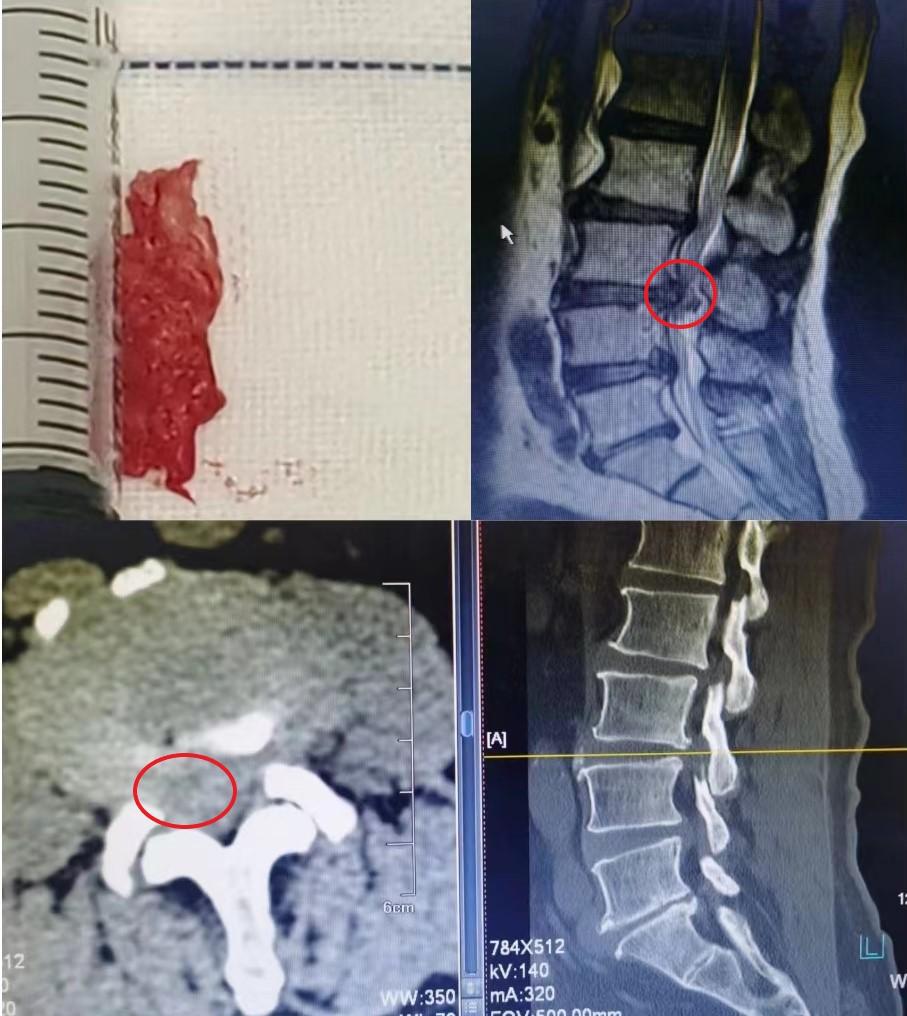

杨希重主任专家团队发现,患者以往就存在的严重的腰椎间盘突出、椎管狭窄,加重了椎间盘组织对神经的压迫,导致了严重的神经损害。当前只有及早行椎管减压,解除神经压迫,挽救患者神经功能。杨希重主任团队为患者进行了腰椎椎管减压+椎间盘髓核摘除+植骨融合内固定手术,术中发现部分髓核组织已经翻转到脊髓的背侧,取出多块脱出的髓核。术后,患者症状缓解,已康复出院。

红圈范围为严重压迫神经的腰椎间盘组织